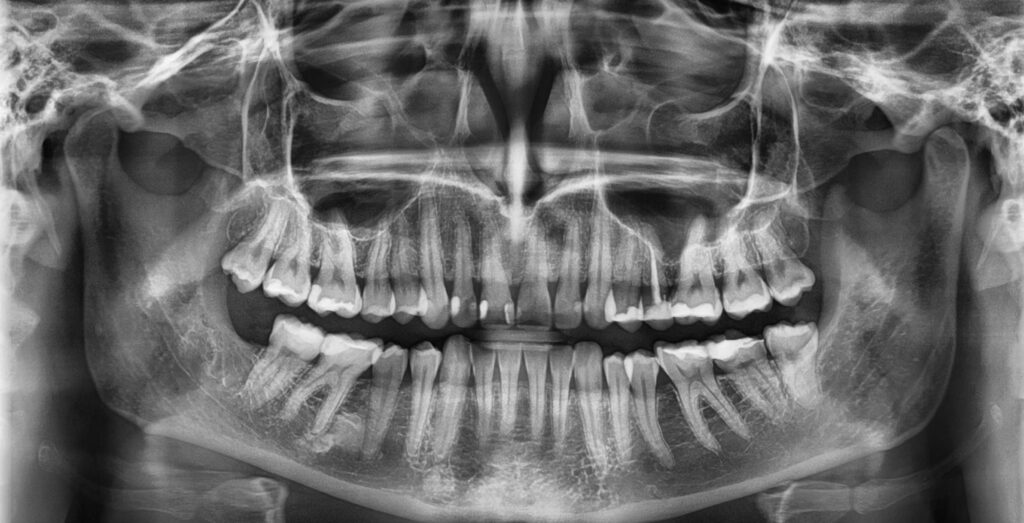

Pantomogram, zwany również zdjęciem panoramicznym, to specjalistyczne zdjęcie rentgenowskie całej jamy ustnej, obejmujące zarówno zęby, jak i szczęki oraz stawy skroniowo-żuchwowe. Jest to podstawowe narzędzie diagnostyczne w nowoczesnej stomatologii, stosowane w klinikach do planowania leczenia zachowawczego, protetycznego, ortodontycznego i implantologicznego. Stomatolog wykorzystuje pantomogram, aby uzyskać pełny obraz stanu uzębienia i otaczających tkanek kostnych pacjenta.

Badanie pantomograficzne pozwala zobaczyć wszystkie zęby, również te niewyrżnięte lub zatrzymane, a także kości szczęk i stawów. Dzięki temu lekarz może szybko wykryć zmiany patologiczne, takie jak ubytki próchnicowe, torbiele, stany zapalne kości czy anomalie zgryzowe. Pantomogram jest również niezastąpiony przy planowaniu implantów, ponieważ umożliwia ocenę ilości i jakości tkanki kostnej.

- Diagnostyka próchnicy i chorób przyzębia – pozwala zobaczyć ubytki międzyzębowe i w kości, które są niewidoczne gołym okiem.

- Planowanie leczenia protetycznego i implantologicznego – umożliwia ocenę ilości i jakości kości oraz położenia nerwów i zatok.

- Ortodoncja Kraków – pomaga w analizie zgryzu, pozycji zębów zatrzymanych i planowaniu aparatów ortodontycznych.

- Chirurgia stomatologiczna – obrazowanie torbieli, zębów zatrzymanych i planowanie ekstrakcji.

Dzięki pantomogramowi stomatolog może planować zabiegi z większą precyzją i minimalizować ryzyko powikłań. Obraz jest podstawą dla leczenia implantologicznego, ponieważ pozwala dobrać właściwe miejsce i kąt wprowadzenia implantu.